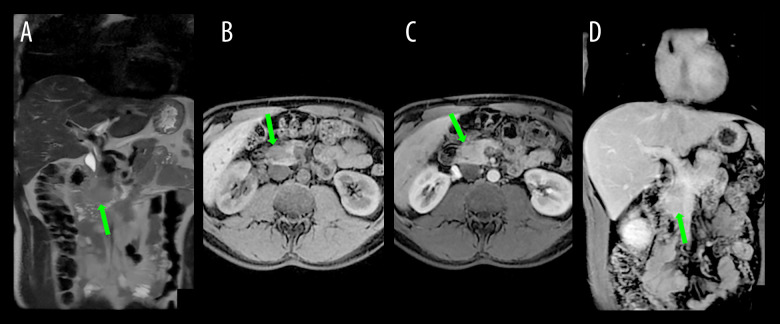

免疫疗法近年来呈指数增长,其相关副作用的研究也呈指数增长。尽管对免疫治疗的广泛反应已被描述,但免疫介导的局灶性胰腺炎的报道仍然很少。与免疫检查点抑制剂相关的自身免疫性胰腺炎发生的原因是T淋巴细胞的过度活化,T淋巴细胞对胰腺细胞起作用,引起炎症。病例报告:本病例报告描述了一位先前健康的41岁男性,诊断为转移性黑色素瘤伴腹股沟淋巴结转移。患者接受了1年的纳武单抗辅助治疗,并具有良好的耐受性。该治疗暂停1年后,淋巴结和腹膜复发发生,导致开始伊匹单抗和纳武单抗联合治疗,随后维持纳武单抗,导致完全缓解。经过10个疗程的纳武单抗治疗后,PET-CT和MRI发现胰腺头部病变,怀疑为原发性肿瘤。患者无症状,肿瘤标志物正常,淀粉酶和脂肪酶水平升高。内镜下超声引导活检排除原发性胰腺癌,发现与免疫治疗相关的中度活动性慢性炎症。尼武单抗治疗中断2周,期间胰酶水平改善。此后恢复治疗。患者继续每月应用纳武单抗,保持完全缓解。成像或实验室检查结果无变化。结论:由于缺乏皮质类固醇干预,炎症的自限性,尽管继续使用免疫治疗,但缺乏炎症复发,该病例是非典型的自身免疫性胰腺炎。

BACKGROUND Immunotherapy has seen an exponential increase recently, as has the study of its associated adverse effects. Although a wide range of reactions to immunotherapy has been described, reports of immune-mediated focal pancreatitis remain rare. Autoimmune pancreatitis related to immune checkpoint inhibitors occurs because of the hyperactivation of T lymphocytes, which act against pancreatic cells, causing inflammation. CASE REPORT This case report describes a previously healthy 41-year-old man with a diagnosis of metastatic melanoma with inguinal lymph node metastasis. The patient underwent 1 year of adjuvant treatment with nivolumab and had excellent tolerance. After a 1-year suspension of this treatment, nodal and peritoneal recurrence occurred, leading to the initiation of combined therapy with ipilimumab and nivolumab, followed by maintenance nivolumab, resulting in a complete response. After 10 cycles of nivolumab, PET-CT and MRI identified a lesion in the head of the pancreas, which was suspected to be a primary neoplasm. The patient was asymptomatic, with normal tumor markers and elevated amylase and lipase levels. An endoscopic ultrasound-guided biopsy was performed to rule out primary pancreatic cancer, revealing moderately active chronic inflammation associated with immunotherapy. Nivolumab treatment was interrupted for 2 weeks, during which pancreatic enzyme levels improved. Treatment was resumed thereafter. The patient continued with monthly nivolumab applications, maintaining a complete response. without changes in imaging or laboratory test results. CONCLUSIONS This case is atypical for autoimmune pancreatitis owing to the absence of corticosteroid intervention, self-limiting nature of inflammation, and lack of inflammatory recurrence despite the continued use of immunotherapy.